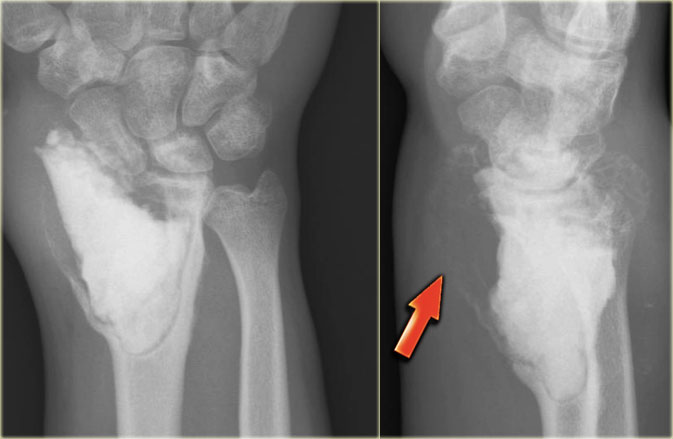

Giant cell tumor (3)

On the left a typical giant cell tumor of the distal radius.

Notice the aggressive appearance with ill-defined borders, extension to the soft tissues and destruction of subchondral bone plate.

The localisation in the epiphysis and metaphysis is in favor of diagnosis of GCT.

On the right a coronal T1-weighted CE image.

There is diffuse heterogeneous enhancement, and extension to the radiocarpal joint and surrounding edema in bone and soft tissues.